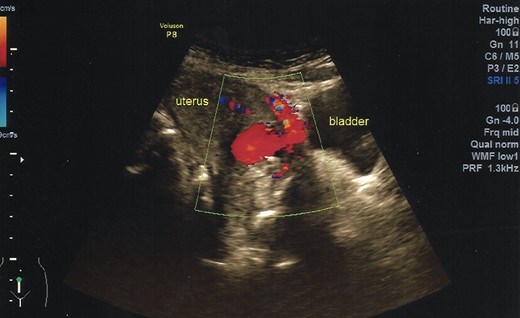

A 40-year-old woman came to the emergency department of the tertiary hospital with vaginal bleeding. She had a history of two cesarean sections (CS), and the last one was 3 years prior without any contraception. She was 10 weeks pregnant and had gone through abnormal uterine bleeding for 2 months. The patient arrived at the emergency department conscious with a blood pressure of 80/40, heart rate of 112 beats/min and hemoglobin level of 11.2 g/dl. Two bags of Ringer’s lactate solution (1000 ml) were given to stabilize the patient. After the patient was stable, a vaginal examination was performed. The cervix was normal, and a small amount of bleeding came out from the external os of the cervix. Ultrasound examination was performed. It showed blood flow in the lower anterior segment of the uterus, but the gestational sac could not be seen, and no intraabdominal bleeding was observed (Fig. 1). However, the pregnancy test pack showed a positive result. The patient underwent observation in the emergency department. At 2 h after admission, the patient underwent profuse vaginal bleeding. The blood pressure was 70/40 with a heart rate of 122 beats/min and decreased hemoglobin level of 6.5 g/dl. The patient consented to undergoing hysterectomy. Laparotomy was performed after hemodynamic stabilization. Intraoperative exploration showed no intraabdominal bleeding. The size of the uterus was normal, no uterine perforation was observed, both adnexa were normal and a bulging mass in the left lower uterine segment was observed without any uterine perforations (Fig. 2). Hysterectomy was performed. The gross specimen indicated a CSP (Fig. 3), which was confirmed by histopathological examination (Fig. 4). The patient received blood transfusion intra- and postoperatively. On Day 3 after surgery, the patient was in good, stable condition and was discharged from the hospital.

Ultrasonography demonstrates a rich blood flow in the lower uterine segment with a normal fundus.

Transabdominal ultrasonography was performed in both patients, which showed a bulging mass in the lower segment of the uterus with a prominent vascularization in both cases. No signs of live intrauterine pregnancy were detected. The gestational sac could not be identified as the image was dominated by blood clots. The fundus of the uterus in both cases was normal without any adnexal mass detected. Several criteria can be used to diagnose CSP in the first trimester by transvaginal sonography: empty uterus, empty cervical canal, gestational sac embedded in the anterior lower uterine segment; and thin or absent myometrium between the sac and the bladder [6]. The main findings from ultrasonography are the implantation of the gestational sac in the previous cesarean scar and the thinning of the anterior myometrium at an average of 3.0 ± 2.0 mm [5]. In patients with excessive vaginal bleeding during early pregnancy, the imaging options are extremely limited. Signs that can be used as a guide to direct the diagnosis of CSP are an early pregnancy with complaints of profuse vaginal bleeding and ultrasonography showing a mass in the lower anterior uterine segment and no intraabdominal bleeding.